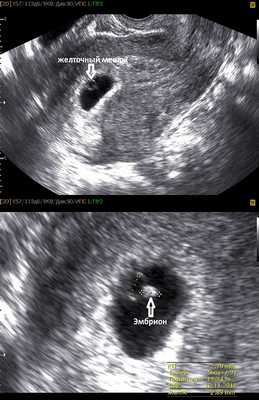

На этом сроке внутри плодного яйца появляется белое колечко - это желточный мешок.

Нормальные размеры желточного мешка 2-6 мм. Если в плодном яйце визуализируются два желточных мешка, значит это монохориальная многоплодная беременность. Но если внутри плодного яйца виден один желточный мешок, а эмбрион ещё отчётливо не визуализируется, то это всё ещё может оказаться монохориальная моноамниотическая двойня.

Эмбрион в начале 5-й недели практически неразличим на стенке желточного мешка, но уже к концу недели копчико-теменной размер (КТР) эмбриона достигает 3 мм.

СВД плодного яйца 11-16 мм.

Внутри плодного яйца мы видим "колечко с драгоценным камнем" :) - это желточный мешок и уже хорошо различимый эмбрион, расположенные рядом. Сердце эмбриона начинает биться в начале 6-й акушерской недели беременности. Именно наличие пульсации сердца является достоверным ультразвуковым признаком прогрессирующей беременности. При КТР ≥6 мм и отсутствии пульсации сердца делается заключение об остановке развития данного эмбриона. Нормальная частота сердечных сокращений (ЧСС) эмбриона в самом начале 6-й недели 70-90 ударов в минуту, но уже к концу недели становится более 100 уд. в мин. На ранних сроках беременности большее значение имеет не ЧСС, а как таковое наличие или отсутствие сердечных сокращений. Иногда, при неразвивающейся беременности можно увидеть отражение пульсации сосудов матери внутри эмбриона и принять их за сердцебиение ребёнка. Но в этом случае частота пульсации будет идентична ЧСС матери.

Наличие одного желточного мешка, одного эмбриона и одного пульсирующего сердца в подавляющем большинстве случаев говорит об одноплодной беременности. Но в очень редких случаях это могут в последствии оказаться неразделившиеся близнецы.

СВД плодного яйца 13-23 мм. КТР эмбриона 4-9 мм.